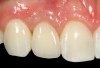

Problem: The implant is placed too facial with significant recession on the midfacial aspect of the abutment and/or crown; the implant is healthy and the patient has a high smile line with an intermediate to thick periodontal phenotype (Figure 1 and Figure 2).17-19

Fig 1. Midfacial recession can affect the esthetics of a smile and lead to an unsatisfactory outcome.

Fig 2. The cause for midfacial recession is excessive labial implant placement. Secondary to poor placement is overcontouring of the implant abutment.